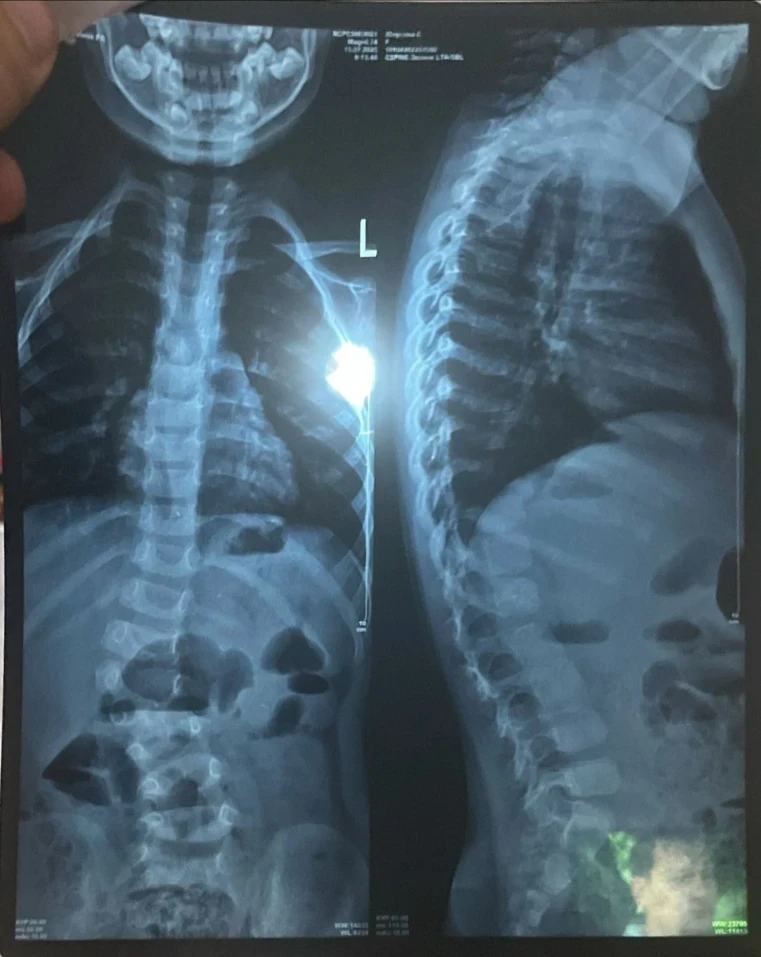

У девочки выявили сколиоз сложной формы, что вызывает у неё затруднения при ходьбе и беге, и она вынуждена проводить большую часть дня в сидячем или лежачем положении.

«Узнав, что ничего не помогает, мы обратились за консультацией к турецким профессорам. Они заявили, что единственный выход — операция, и чем быстрее она будет проведена, тем лучше для роста и развития Сумаи. Кроме того, мы узнали, что у неё есть лишняя кость на позвонке, что также является последствием сколиоза», - сообщает мама.

Сколиоз уже вызвал асимметрию тела, у Сумаи одно плечо ниже другого, а одна нога короче.